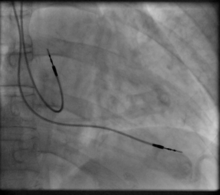

Transvenous pacing (temporary)

Transvenous pacing, when used for temporary pacing, is an alternative to transcutaneous pacing. A pacemaker wire is placed into a vein, under sterile conditions, and then passed into either the right atrium or right ventricle. The pacing wire is then connected to an external pacemaker outside the body. Transvenous pacing is often used as a bridge to permanent pacemaker placement. It can be kept in place until a permanent pacemaker is implanted or until there is no longer a need for a pacemaker and then it is removed.

Permanent pacing with an implantable pacemaker involves transvenous placement of one or more pacing electrodes within a chamber, or chambers, of the heart, while the pacemaker is implanted inside the skin under the clavicle. The procedure is performed by incision of a suitable vein into which the electrode lead is inserted and passed along the vein, through the valve of the heart, until positioned in the chamber. The procedure is facilitated by fluoroscopy which enables the physician to view the passage of the electrode lead. After satisfactory lodgement of the electrode is confirmed, the opposite end of the electrode lead is connected to the pacemaker generator.